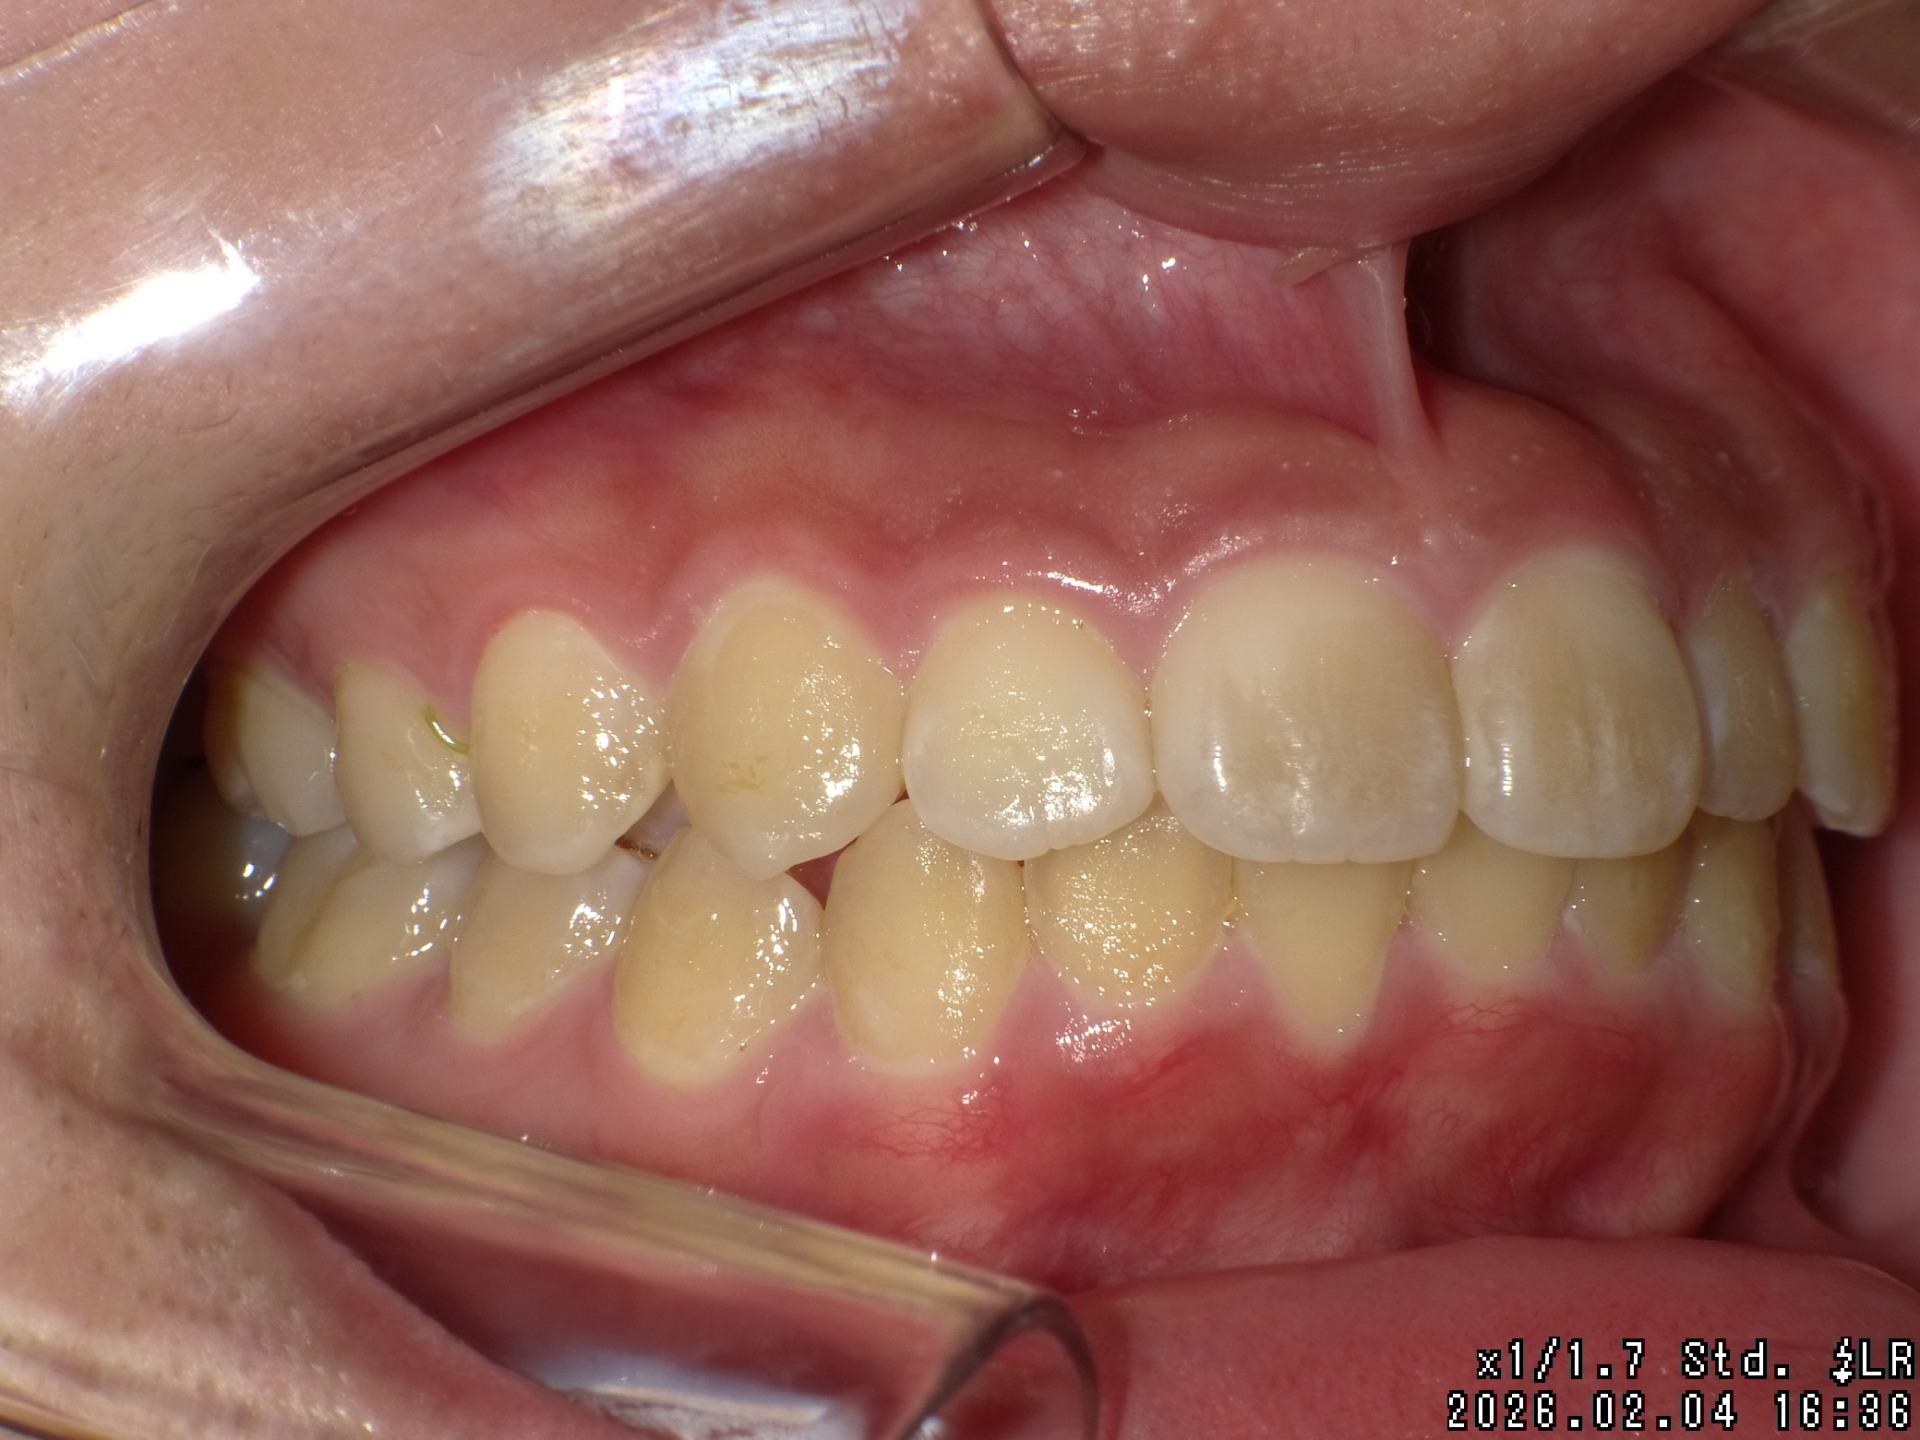

矯正前

| 症状 | 上顎前突 過蓋咬合 |

|---|---|